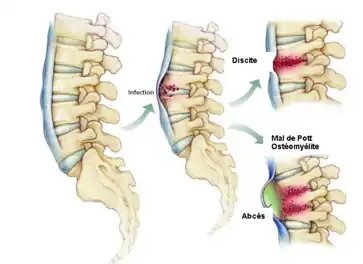

Tuberculose ostéoarticulaire

La forme la plus fréquente et la plus redoutable est la tuberculose rachidienne dite mal de Pott. La localisation au niveau de l’espace intervertébral (mal de Pott) est la plus fréquente des localisations ostéoarticulaires et la plus grave car elle siège au voisinage des structures nerveuses importantes. Elle représente 10 % des cas de tuberculose[60].

La phase initiale de l’infection est marquée par l’atteinte des espaces intervertébraux rachidiens, et l’atteinte de la synoviale, où se développe la lésion tuberculeuse laissant apparaître une symptomatologie plus ou moins spécifique marquée par : des douleurs au niveau du rachis de type mécanique ainsi qu’un syndrome infectieux modéré et des signes de déficit neurologique s’installant progressivement[62]. Si elle est dépistée et traitée à ce stade d’invasion, l’évolution se fait vers la guérison et sans destruction.

En revanche et en absence de traitement, l’évolution se fait lentement à partir d’un état stable vers la phase d’état où la destruction est irréversible. Sur le plan tissulaire, on remarque une lésion spécifique à la tuberculose : la nécrose caséeuse développée dans l’espace intravertébral et laissant des séquelles majeures et irréversibles. La symptomatologie est variée et marquée par des douleurs intenses avec une tuméfaction de la région affectée et adénopathie du site drainant la région ainsi que les troubles neurologiques.

Le clinicien oriente vers les examens complémentaires afin d’affirmer son diagnostic et cela à travers la radiologie qui fournit des images plus ou moins spécifiques et la mise en évidence du BK via l’examen bactériologique et anatomopathologique à la suite d'une ponction/biopsie réalisée sur le site de l’infection.